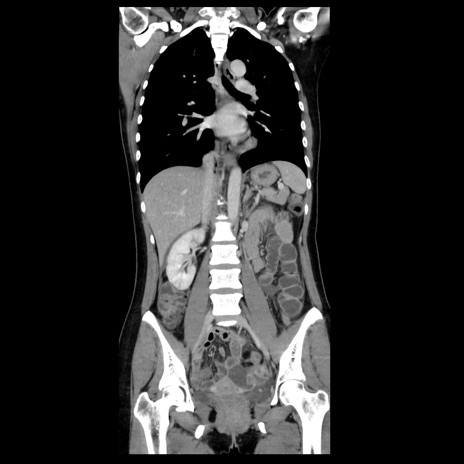

症例39(冠状断像)

【症例】40歳代女性

【主訴】上下腹部痛

【現病歴】2日目から下腹部痛あり。夜間は痛みで眠れなかった。昨日より上腹部痛と下痢が出現。臥位で痛みは軽快したため、休んでいた。本日になって臥位でも立位でも痛みが強くなってきたため救急要請。

【既往歴】子宮内膜症

【身体所見】部:平坦・軟、左上下腹部に圧痛あり、反跳痛あり。

【データ】WBC 21800、CRP 26.78

CT